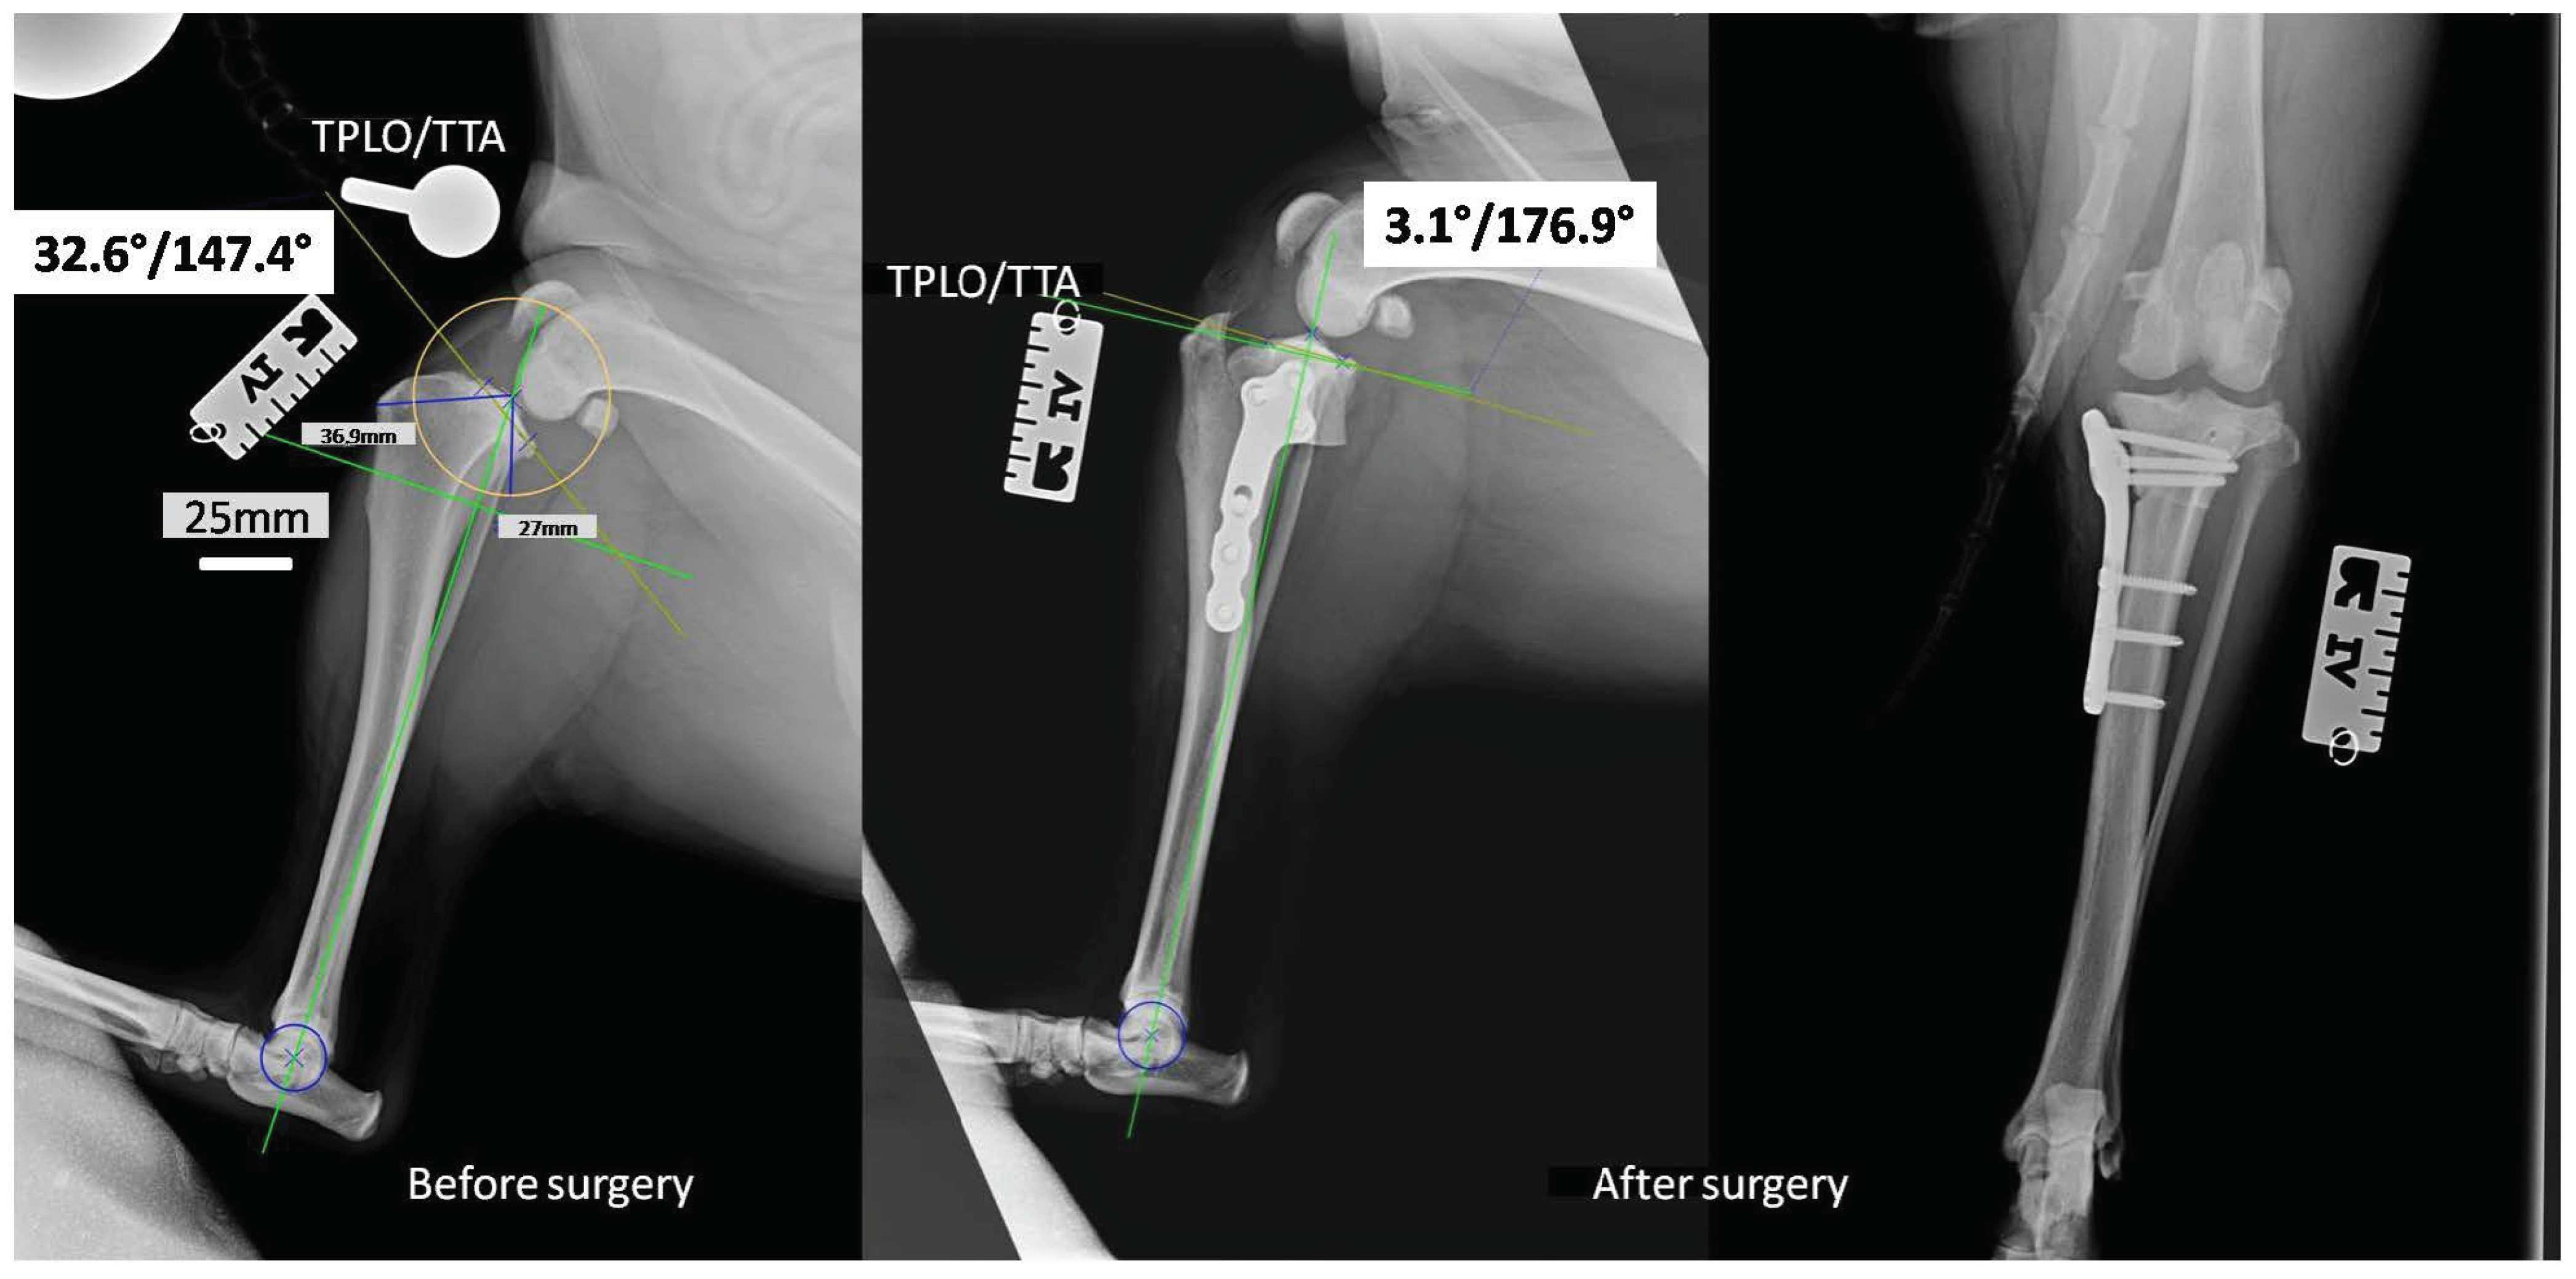

2.2. In Vivo Study

4.8. Tibial Plateau Leveling Osteotomy (TPLO)

4.9. Radiological Examinations